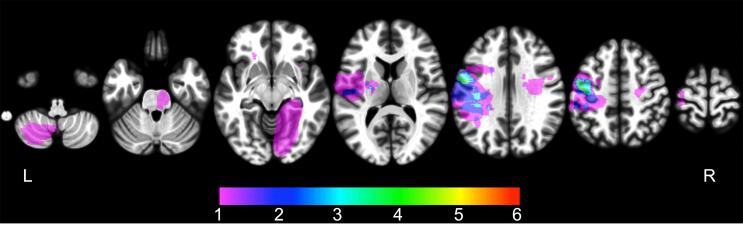

Fig. 4.

Lesion (functional) network mapping results.

Regions of overlap among 25 FAS lesion-seeded networks are shown in red. The main cluster is located in the bilateral insula, lower portion of the prefrontal gyrus, medial frontal cortex, and upper middle portion of the prefrontal gyrus. The maximum number of overlapping cases was 23 (92%), which was higher than with the traditional lesion overlapping method. These results are illustrated using the Mango visualization software (http://ric.uthscsa.edu/mango/). Axial coordinates refer to MNI space.

In contrast, lesion (functional) network mapping analysis revealed that the overlap ratio of lesion-derived functional networks was quite high (~92%), and network overlap was observed specifically within the motor speech area involving the bilateral middle portion of the precentral gyrus ([48, 2, 43] and [−37, −10, 43] in the MNI space), the bilateral lower portion of the precentral gyrus extending to the insular cortex ([32, −5, 14] and [−24, 2, −18] in the MNI space), and the medial frontal cortex corresponding to the supplementary motor area (SMA) ([-8, 11, 31] in the MNI space) (Table 2, Fig. 4). Twenty of 25 FAS lesions were also functionally connected with the left parietal opercular cortex, the bilateral thalamus, and the bilateral cerebellum (lobule VI), in which the cluster sizes were relatively small (Table 2). All lesions were positively correlated with these brain sites, and no other areas of network overlap (positive or negative) met our threshold (80% overlap).